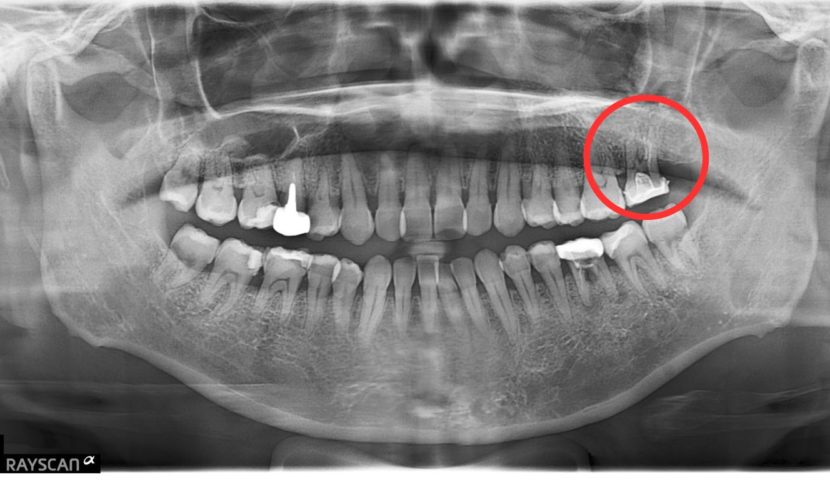

インプラント治療は、近年長期安定性が見込める治療になってきました。10年予後が下あごで99%、上あごで96%とも言われております。当院では、過去に歯を失ってしまって後悔されている方に対しても、お一人お一人にとってのベストな歯科治療をご提供できるようにしております。